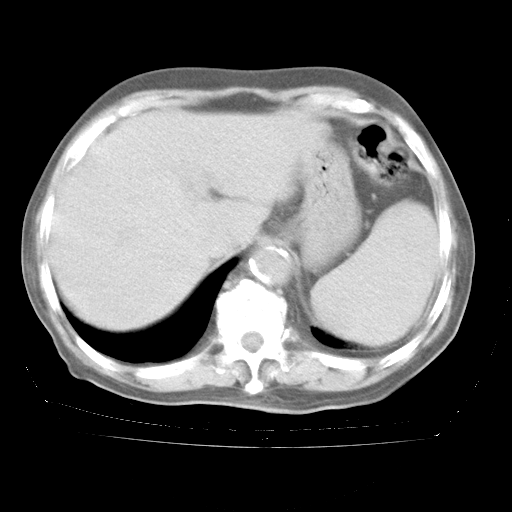

4月28日肺部CT——再次出现类似去年5月9日——透光度降低,“间质性”改变。

4月28日肺部CT——再次出现类似去年5月9日——磨玻璃样、间有“粟粒样”改变。

4月28日肺部CT

个人阅读4.14日肺部CT平扫:纵隔窗无异常,但肺窗示:双下肺内、后基底段有片絮状侵润影,部位以后基底段为著,以间质改变为主,呈急性肺泡炎征像,和首次住院影像学有相似之处。仅是个人读片,明日请相关专家再读片哈。其它建议同上。

1、108#的是4月14日的胸部CT(发此贴时还没看着28日的CT)。14日的胸部CT其实已经出现改变(如108#所述),个人认为28日的胸部CT除纵膈窗疑似有双侧胸膜增厚或少量胸积液(可行胸部B超明确)外,与4月14日对照病变有所加重;2、已经给予“异烟肼、利福平、乙胺丁醇”抗痨治疗?如果是,甲强龙80mg可缓慢减量;如果环磷酰胺已停用,暂不使用;3、中性粒细胞92%,明显升高,目前体温情况?注意合并细菌感染可能,使用左氧氟沙星情况下,是否联用B-内酰胺类抗菌药物?另外是查免疫全套非风湿全套。

今请临免主任会诊后认为:4月14日胸部CT已有双下肺间质性改变。患者病情复发多系激素减量过快不正规所致。目前甲强龙80mg/日,一周后酌情开始减量,不易过快。环磷酰胺若已停用,暂不使用。他同意目前抗菌药物使用,但应考虑是否加用B-内酰胺类抗菌药物(中性细胞明显增高);2、结核复发目前依据不足;3、若免疫全套各项指标正常,考虑多系特发性肺间质炎可能大。4、加强支持,并注意保护胃黏膜。

今上午去请教了临免、呼吸主任:1、介绍病史和阅读系列胸部CT一致认为:患者肺结核不考虑,仍为肺间质纤维化,目前处于急性肺泡炎阶段。2、若仍发热,可将甲强龙增至:80mg Bid静滴,同时鉴于中性增高,合并细菌感染可能,继续左氧氟沙星治疗,再联用B-内酰胺抗菌药物,如头孢哌酮--舒巴坦;3、停用抗痨药;4、目前甲强龙每日剂量160mg ,体温正常后再酌情减量;目前暂不用免疫抑制剂;4、不建议使用免疫增强剂等;5、加强支持治疗,鼓励患者进食;5、注意随访肝、肾功及血常规情况;6、因患者目前激素用量较大,加用胃黏膜保护剂,防止消化道出血可能。